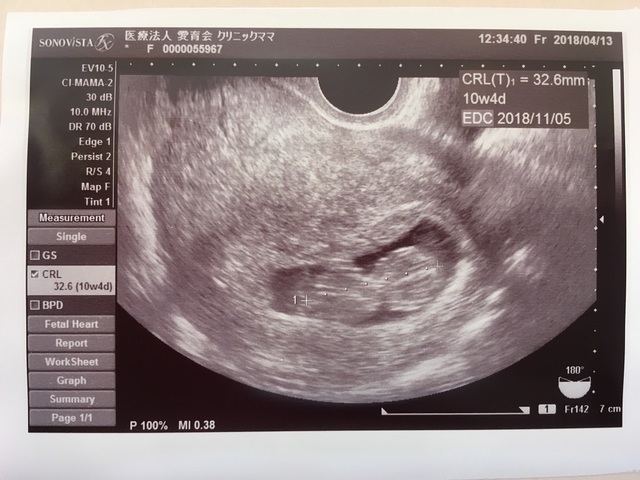

10週4日(10w4d・女の子)|ウンザウンザ さん(29歳)

エコー写真撮影時のエピソード:

初めての妊娠では流産を経験しました。 今回も流産してしまうのではないかと毎回不安な気持ちで検診を迎えましたが、初めて卵の形から人らしい形に成長していて、感動したのを覚えています。 その後も無事に育ってくれて、元気に生まれてきてくれました。